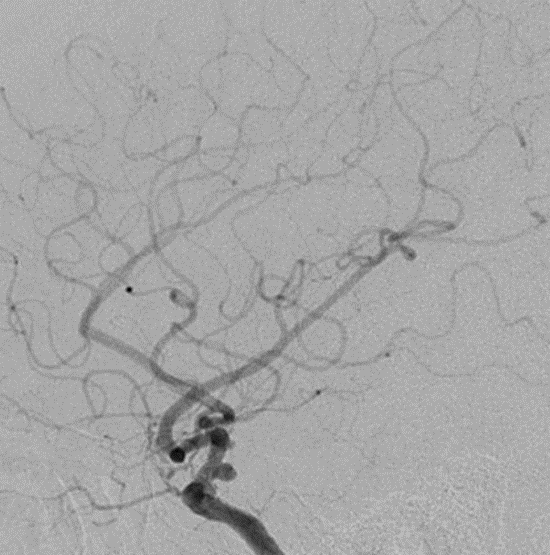

脑血管造影提示右侧颈内动脉颅内段多发动脉瘤(反主动脉弓)

脑血管造影提示右侧颈内动脉颅内段多发动脉瘤

4mm×30mm Streamline

术后4月余随访:多发动脉瘤均未见显影,远端残余轻度狭窄

术前术后对比